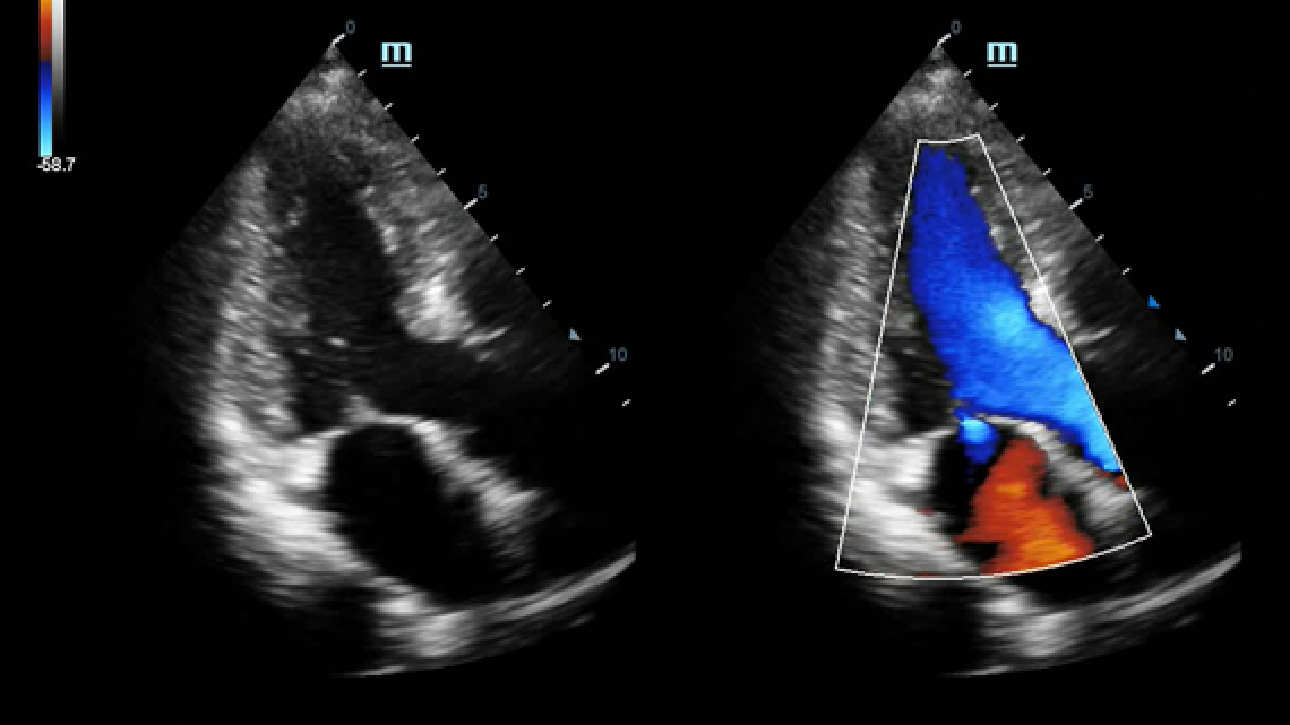

LVO (Left Ventricular Opacification)

Reveal structural and functional change of left ventricle with longer contrast agent duration and higher sensitivity with UWN+ technology.

Echo Boost

MindrayŌĆÖs unique adaptive signal processing technology with intelligent echo detection, designed to utilize the native signal-to-noise information to enhance the weak echo signals while suppressing the surrounding clutter noise, providing more balanced image brightness and improved visualization of myocardium tissue layers.